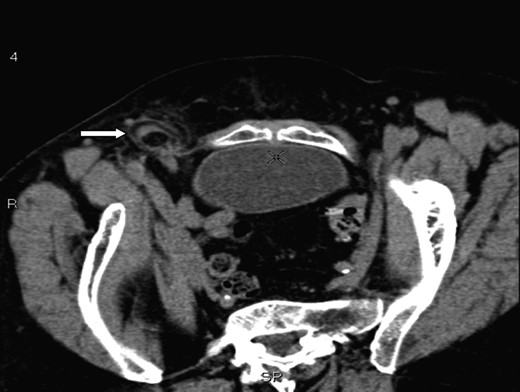

A 70-year-old female was referred by her general practitioner to our radiology department after presenting with a painless right groin swelling. An ultrasound scan showed a lymph node in the right groin with surrounding fluid and unusual appearances not typical of a hernia. A limited CT scan was subsequently performed which revealed a right femoral hernia containing the tip of the vermiform appendix with surrounding inflammatory change and an associated enlarged lymph node in keeping with a De Garengeot's hernia (Figs 1–3). On questioning, the patient first noticed the lump 2 weeks prior to presentation and said that it has gradually increased in size. It was not painful and she had no obstructive symptoms. Her medical history included COPD, breast cancer and a past history of tuberculosis.

A saggital section demonstrating the tip of the appendix (white arrow) within the femoral sac.